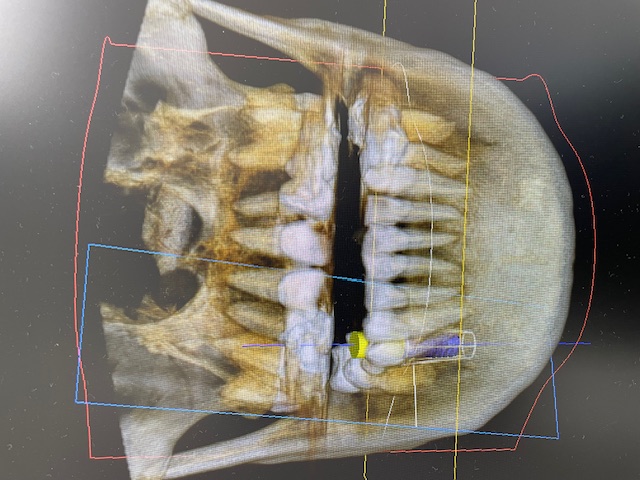

歯科用CT

CT

歯や顎の状態を3次元の立体画像で確認できます。